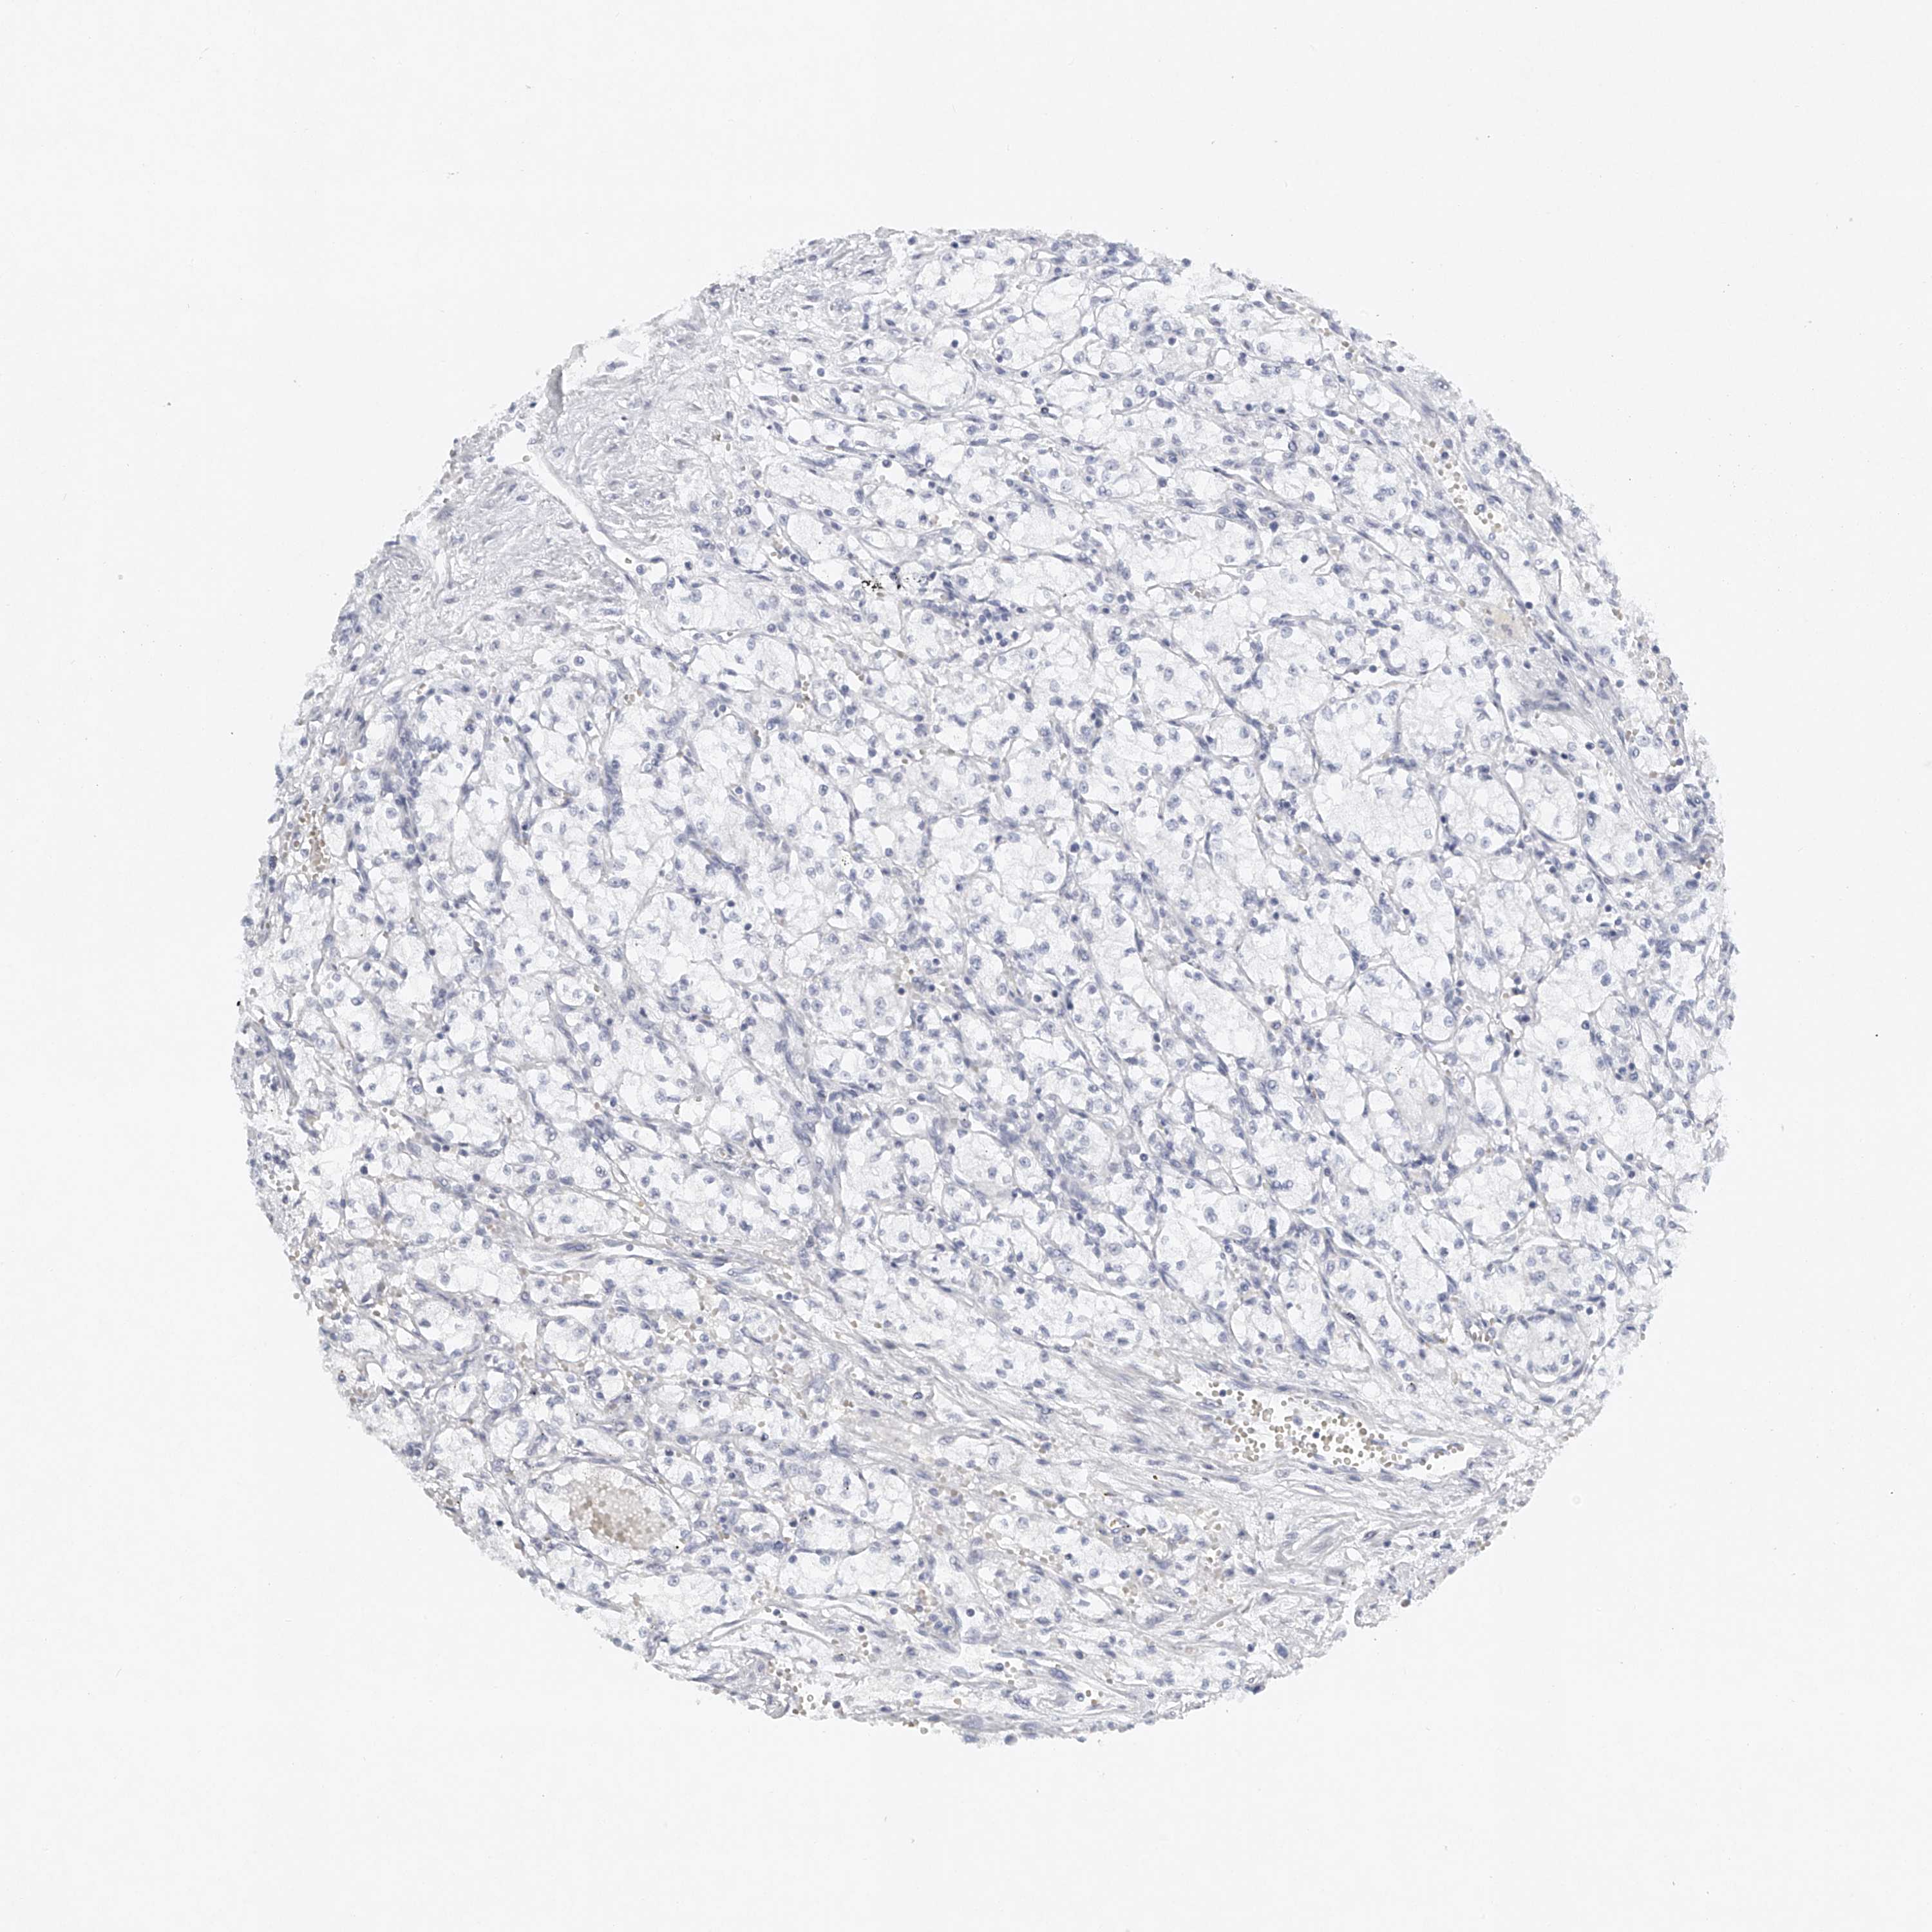

CANCER RENAL CANCER Show tissue menu

KICH TCGA KIRC TCGA KIRC VALIDATION KIRP TCGA PROTEIN RCC CPTAC PROTEIN EXPRESSION